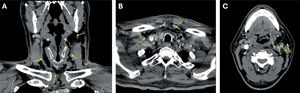

Fascitis necrotizante cervical: una complicación infrecuente